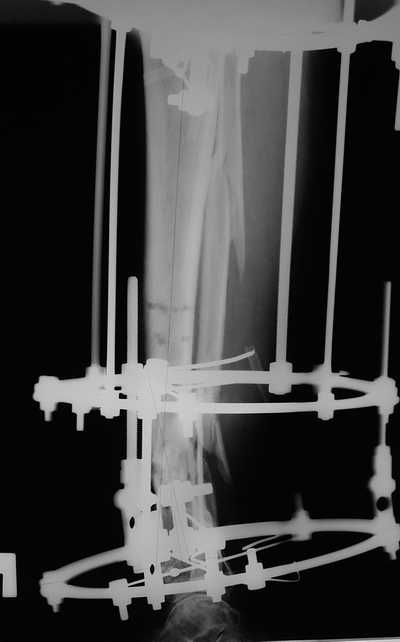

Male 54 years old, diabetic, blind in both eyes, with infected (MRSA) non union distal tibia after fracture 8 month ago. In acute phase treated by ORIF with LCP tibia and fibula. Treatment complicated by infection and after 6 month hardware was removed and treatment continued by cast fixation. You can see malposition of fragments In this stage beginning treated by Ilizarov fixation with use Hexapod system, allows anatomical position of fragments and you see signs of union.

Женщина 46 лет, неудачно лечившаяся по поводу перелома голени в нижней 1\3 сначала в гипсе, поступила через 6 месяцев после остеосинтеза пластиной (рис 1). Имелась деформация в нижней 1\3 голени: варус, антекурвация, наружная ротация, два свища. Удалена пластина, дебридмент мягких тканей,

остеотомия м\б кости, аппарат Илизарова. По рентгенограммам в двух проекциях произведено планирование устранения смещений (рис 2 и 3), между вторым и третьим кольцом установлены 6 телескопических дистракторов Гесапода, данные введены в программу, и далее втечение 10 дней больная подкручивала телескопы согласно выданной компьютером инструкции. По завершению репозиции гексаподные телескопы обратно заменены на обычные штанги от аппарата Илизарова (рис 4 и 5). Еще через две недели забит гвоздь (рис 6, контроль

через 4 месяца).